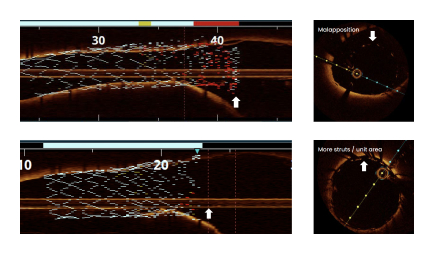

Suboptimal Lesion Coverage

Standard PTCA catheters are unable to create a smooth transition at the ostium creating suboptimal lesion coverage, which is associated with poor outcomes.1

of lesions demonstrated complete stent apposition2,3